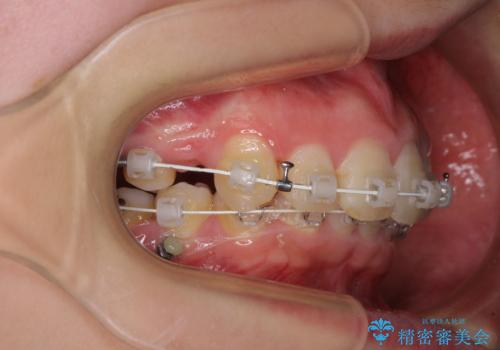

上顎前突を改善するために上顎左右第一小臼歯を抜歯し、補助装置を用いて上顎臼歯が前方に移動しないように工夫しながら、表側のワイヤー装置にて歯列を整えていくこととしました。

矯正治療後には、上顎欠損部をオールセラミックブリッジにて補綴治療を行うこととしました。

予想通りに治療は困難を極め、その上途中来院されない時期があったため、非常に長期間に及びましたが、周囲の方々が驚愕するほど口元の印象を改善することができました。